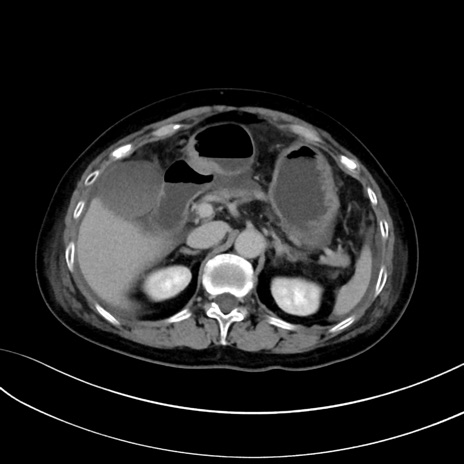

症例13 CT(横断像)1日半後

(冠状断像)1日半後